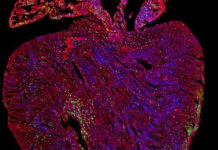

Los científicos en el Grupo de Investigación de Thomas Braun en el Instituto Max Planck para la Investigación del Corazón y del Pulmón han logrado identificar una población de células madre en ratones que juega un papel clave en esta regeneración de las células del músculo del corazón. Los experimentos realizados por los investigadores en Bad Nauheim con ratones genéticamente modificados muestran que las células madre Sca1 en la salud del corazón están involucradas en la sustitución continua de las células del músculo del corazón. Las células Sca – 1 aumentan su actividad si el corazón está dañado, con el resultado de que se forman las células significativamente más nuevos del músculo del corazón.

«También se enfrentan al problema de que SCA1 ya no está disponible en las células como una proteína marcadora de células madre después de que han sido transformadas en células de músculo cardíaco. Para probar esto, tuvimos que ser creativos», dice el líder del proyecto Shizuka Uchida. Los investigadores del Instituto Max Planck modificaran genéticamente las células madre hasta el punto de que, además de la SCA1, se produjo otro marcador visible. Incluso si SCA1 estaba posteriormente no es visible, el marcador todavía podría ser detectado de forma permanente.

«De esta manera, hemos sido capaces de establecer que la proporción de las células del músculo del corazón se originan en células células madre SCA1 que aumentan continuamente en ratones sanos. Alrededor de un cinco por ciento de las células musculares del corazón regenera a sí mismas dentro de los 18 meses», dice Uchida. Por otra parte, los ratones que sufren de enfermedades del corazón provocada por el experimento tenían hasta tres veces más de estas células del músculo cardíaco recién formadas.